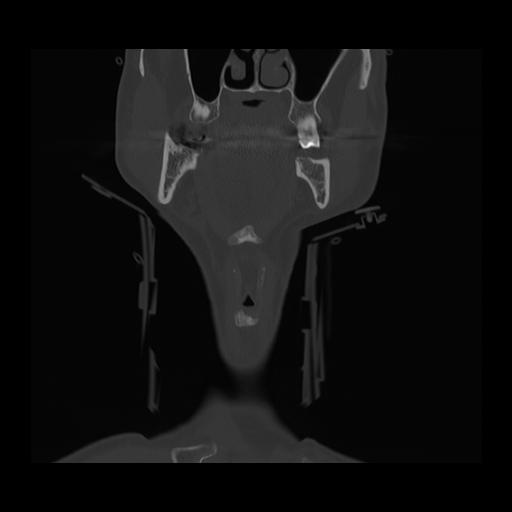

16 HUESO,,Coronal,2.000,HUESO,Coronal,